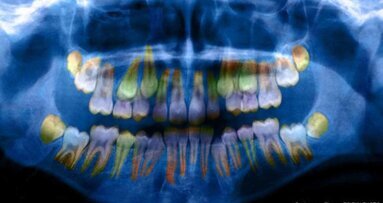

Een professor dentale beeldvorming aan de KU Leuven liet de vier ingenieurs van Relu weten dat ze veel interesse had in het model. Het model zou bij het gebruik van CBCT-scans kunnen worden ingezet, aangezien dit een erg tijdrovende bezigheid is. Op basis van die scan moet namelijk nog een gedetailleerde tekening van de anatomie gemaakt worden.

Het 3D-model kan op basis van CBCT-scans 3D-modellen van de kaken, tanden, de schedel, de sinussen en de kaakzenuwen maken. Die verschillende modellen worden dan samengevoegd tot een geheel, een soort ‘virtuele patiënt’. Dit proces duurt enkele seconden.